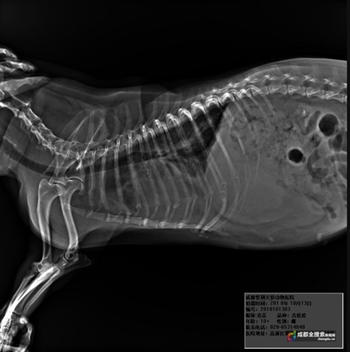

徐医生告诉记者,这只狗狗的品种为吉娃娃,根据判断,年龄应该在13岁以上,身上有些许外伤,可能遭到过殴打,在被送进医院当天就对其做了检查,诊断出了心衰,肝衰竭,肝脏胀大,肝功受损,腹水胸水,等多重问题,“可能曾经是家养的宠物狗,要么是被遗弃,要么走丢了,如果是野狗的话,会更脏。”徐医生说,正常情况下的狗,在这个年龄段的体重为8斤左右,可是它的体重有13斤,“它不是胖,相反,它非常瘦,多出来的体重就是肿瘤,积水。”

一个星期以来,医院一边细心治疗,一边仍在检查是否还有其他病症,“看它呼吸急促,我怀疑可能有胸腔肿瘤,虽然心衰也会导致浮肿,但是一般都是脚肿,肚子肿,不会肿到脸上去,如果要确认就只有打CT,但是那需要全身麻醉,以它现在的身体状况,肯定不能负担。”为了尽量去治好,在药物方面,医院对其使用了保肝,强心,利尿等功能的药品,还有足够的营养供给,但目前看来,状况并不乐观,“也不敢给它输液,一输液就怕增加它心脏的负担,打针、吃药,给它用了很多药了,效果都不好。最后治得好不,不好说,估计它肯定会预后不良,就看它造化了。”